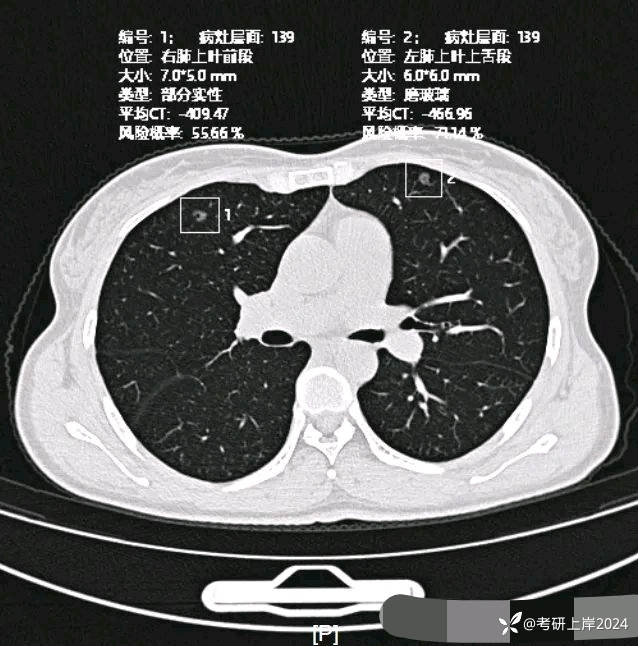

患者最近的检查有AI辅助诊断意见,找出的病灶分别如下:

病灶1:右上叶长径8毫米纯磨玻璃结节,边上有微小血管贴着,整体轮廓较清,怕哪样欠均匀。考虑不典型增生或原位癌可能性大;

病灶2:右上叶长径7毫米磨玻璃结节,密度稍高,但仍未达纵隔窗可见的实性密度,中间有小空泡征,轮廓与边界清,考虑原位癌或微浸润性腺癌可能性较大;

病灶12:左上叶磨玻璃结节,轮廓较清,有血管穿行,考虑肺泡上皮不典型增生可能性较大,也可能原位癌;

病灶17:左上叶磨玻璃结节,伴小空泡征,也有微血管征,考虑原位癌可能性较大。